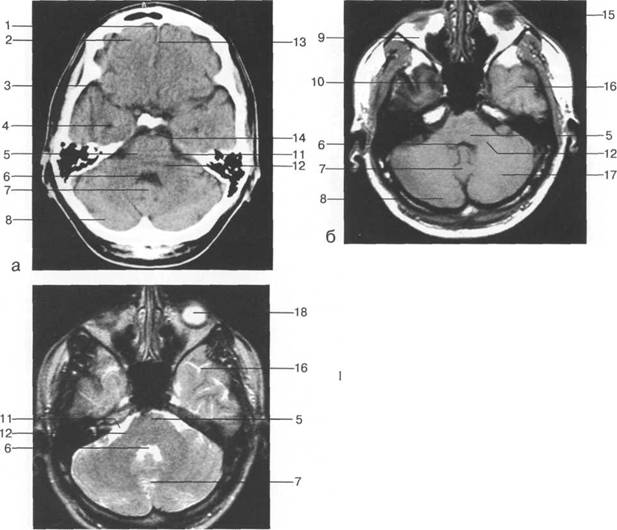

Задняя череп 13513u2010n 85;ая ямка представляет собой часть основания череп 13513u2010n 72;, ограниченную централь

Следует отметить, что в настоящее время оптимальным методом исследования структур задней череп 13513u2010n 85;ой ямки является МРТ, которая, в отличие от КТ, лишена артефактов от кост

Мозжечок заполняет практически весь объем задней череп 13513u2010n 85;ой ямки. Его поперечный раз

IV IV IV IV III IV

височная доля; 17 - полушарие мозжечка; 18 - |

Следует остановиться на анатомии подпаутинных пространств задней череп 13513u2010n 85;ой ямки IV 20 мм. Между основанием череп 13513u2010n 72; и нижней поверхностью мозга от большого затылочного отверстия вдоль ската и спинки турецкого седла простирается задняя базальная цистерна. В зави IV